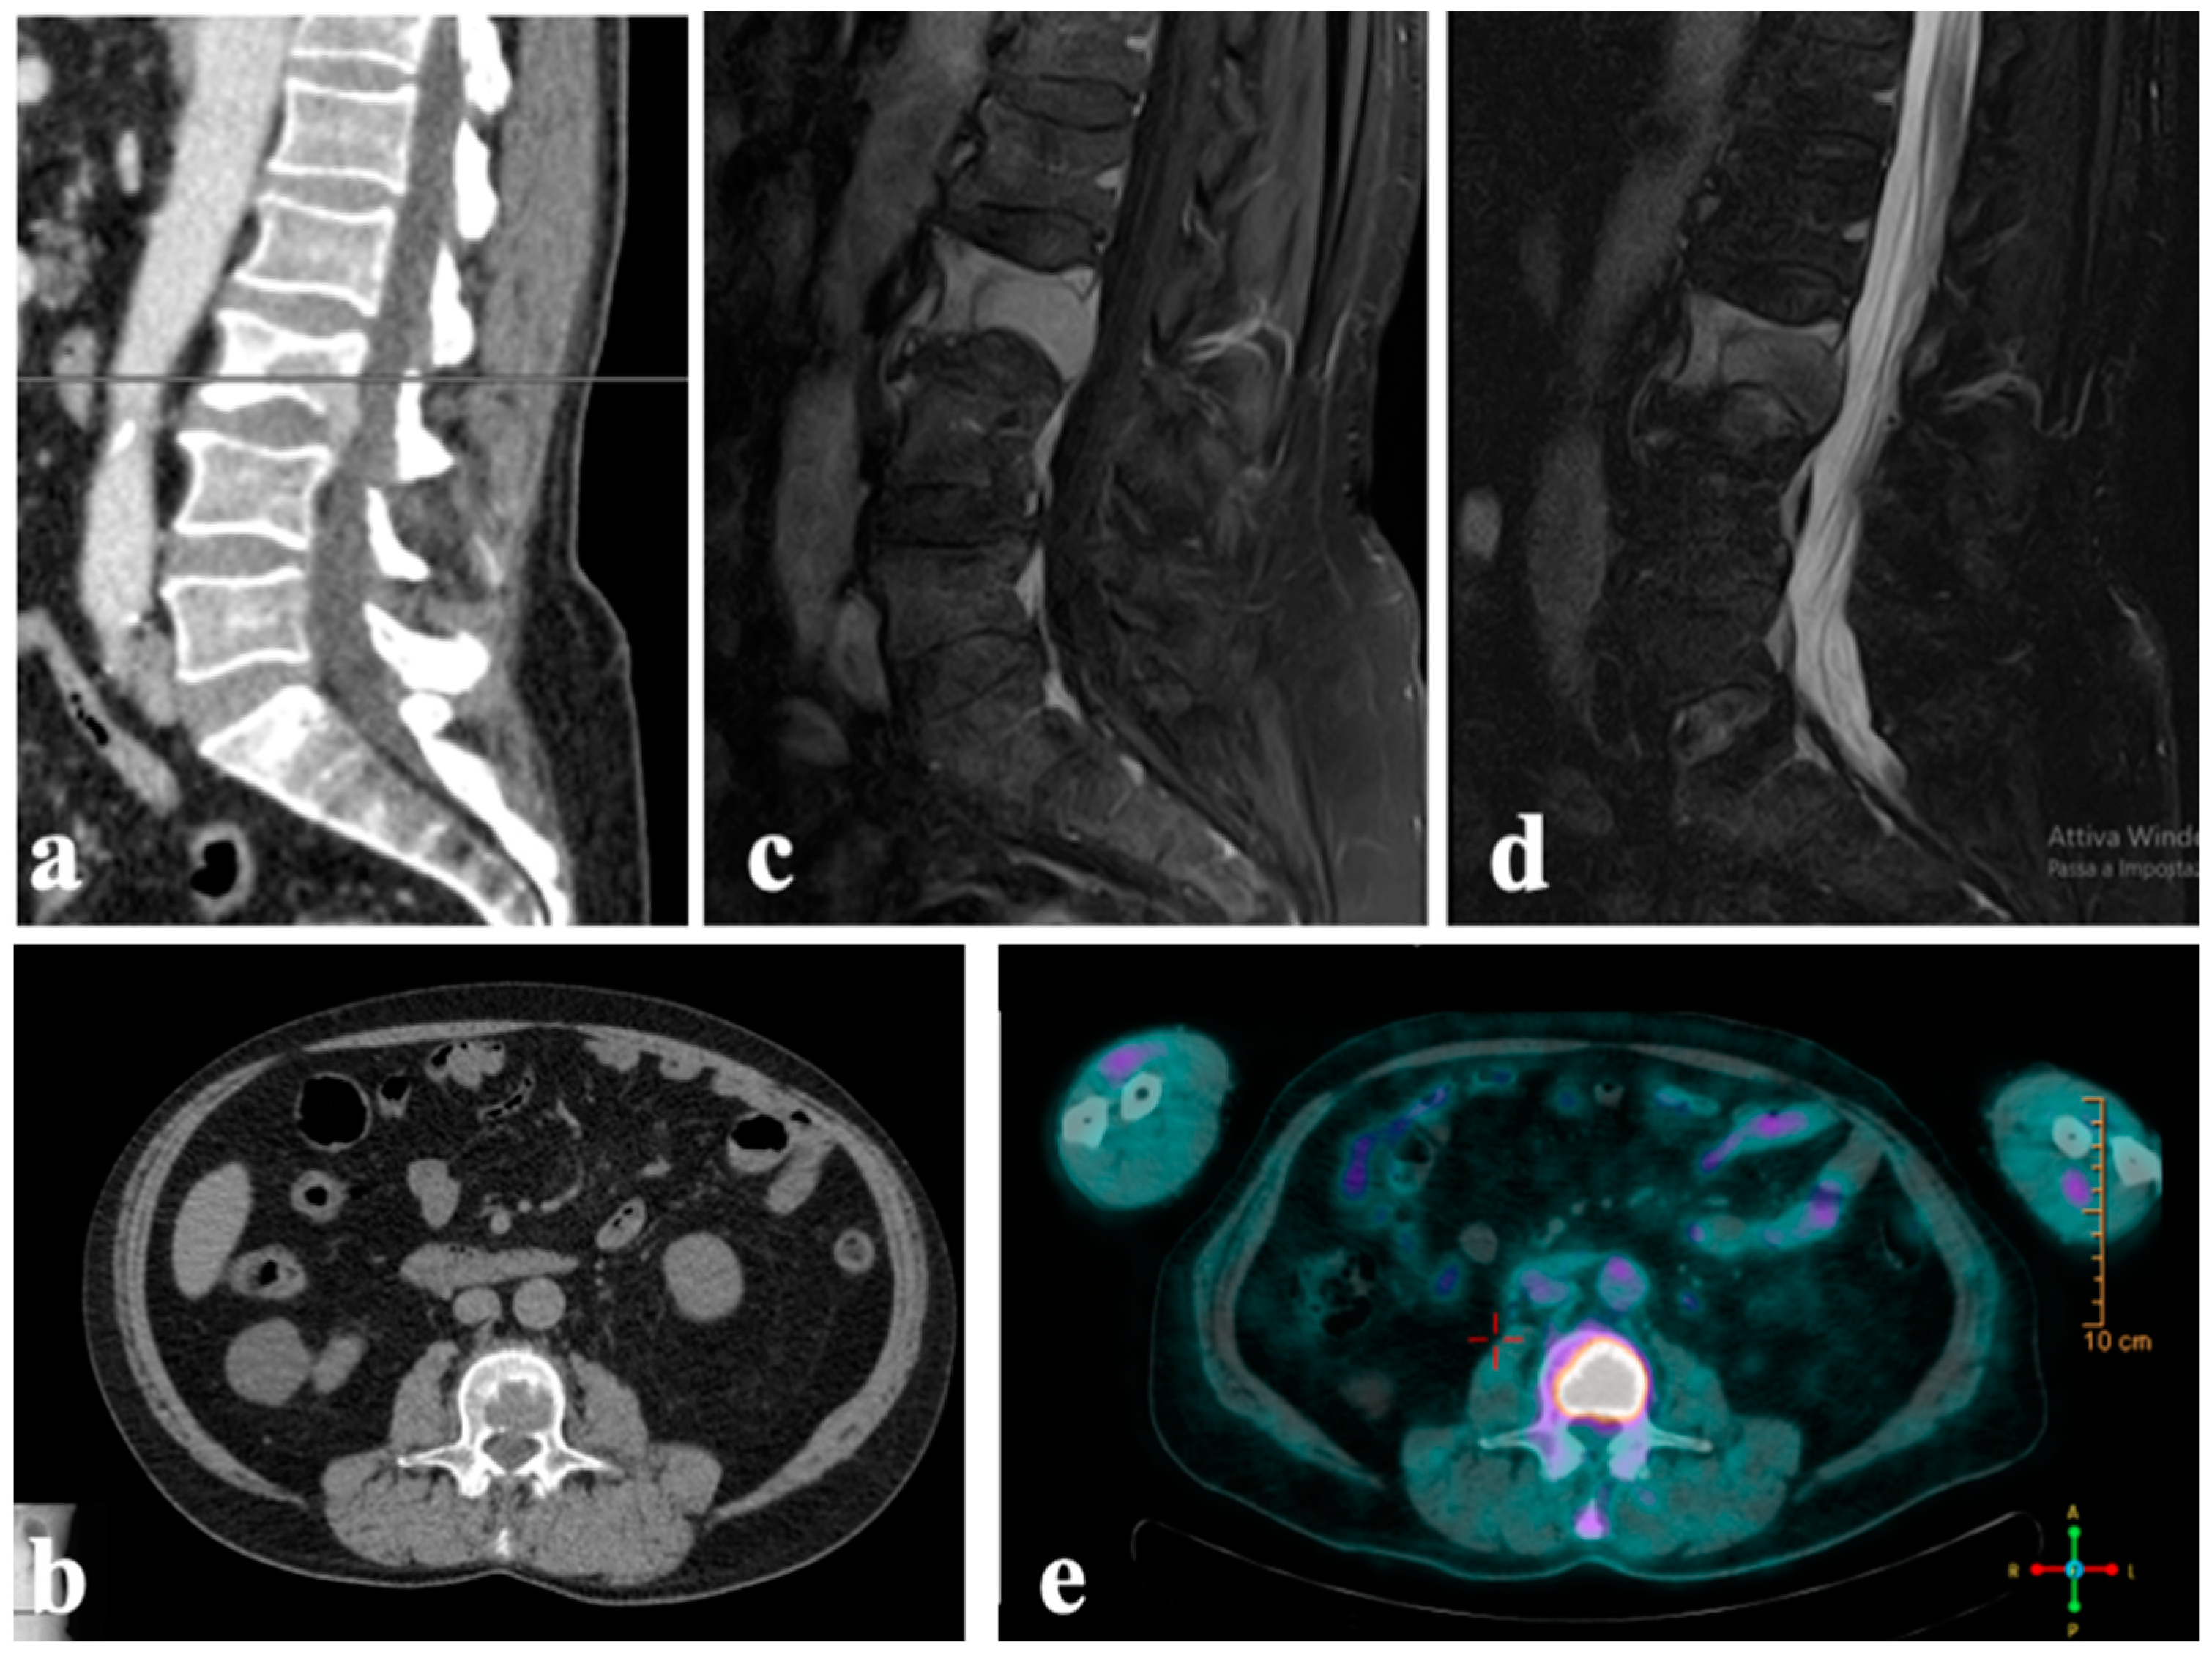

Follow-up assessments, comprising both clinical and radiological examinations, were scheduled at one- and four-week post-surgery, followed by three-month intervals thereafter. The evaluation of the patient’s reported outcomes using the Visual Analog Scale (VAS) revealed a statistically significant reduction from 10 to 2 (p < 0.001). However, no significant changes were noted in the patient’s neurological status, and there were no local or general side effects observed either immediately after waking or during postoperative follow-up. Imaging restaging conducted 3 months after surgery (Figure 5) demonstrated no signs of implant loosening, and the size of the tumor at the L3 vertebra remained stable. Unfortunately, the patient passed away at 4 months of follow-up due to respiratory failure caused by the progression of metastatic disease to the lungs.

Figure 5.

Case 1. Radiographs taken 3 months after surgery demonstrate no signs of implant loosening.

A 76-year-old female patient with a history of squamous cell carcinoma of skin in the lumbar area, which was surgically removed in November 2022 with clear surgical margins, and abdominal scleroatrophic lichen presented to our spinal surgery center with symptoms of spinal cord compression. These symptoms included a 2/5 strength deficit in the quadriceps femoris, psoas, and right adductor muscles; bilateral patellar and midplantar hyporeflexia; absence of clones; negative Babinski sign; and preserved sensitivity in the lower limbs.

Upon instrumental examination (whole-spine MRI), an osteolytic lesion was observed on the vertebral soma of D12 (Figure 6), along with a pathological fracture and medullary compression.

Figure 6.

Case 2. A 76-year-old woman with T12 metastasis from squamous cell carcinoma: (a,b) preprocedural MRI in sagittal and (c,d) axial plane showing the complete involvement of anterior vertebral body and partial cord compression.

A 73-year-old male patient with no history of tumor presented with swelling in the left ankle for about a year, with a notable increase in size in the last 3 months. An MRI of the left ankle showed a soft-tissue lesion in the distal third of the leg with no erosion of the bony cortex. A needle biopsy with histological evaluation was performed, resulting in the diagnosis of leiomyosarcoma G3 with areas of necrosis (30%) desmin +, caldesmon +, and smooth muscle actin +. A below-knee amputation was performed with histological confirmation of both tibial and fibular bone infiltration and wide margins.

During follow-up, a CT scan of the chest and abdomen for restaging showed multiple metastases in the pectoral region, left gluteal region, left ischiopubic branch, and the vertebral soma of D11, with the involvement of the posterior wall and partial spinal cord compression (Figure 8a,b). Given the effective pain control and the absence of neurological symptoms, conservative treatment with a spinal brace was proposed for the thoracic metastatic lesion, along with chemotherapy. During the first month, the patient experienced clinical worsening (ASIA scale D), reporting an increase in pain to VAS and a decline in oncological indices (Karnofsky 50%, Tokuashi 9, and Tomita 6). Therefore, surgical treatment was considered. Surgery consisted of spinal cord decompression in D11, spinal stabilization from D10 to L1, and ECT with bleomycin administered at the D11 vertebra (Figure 8c–f), with immediate pain relief (VAS 2) and neurologic restoration (ASIA scale E). The patient was alive with disease at the 6-month follow-up, with stable disease observed in the vertebral site.

Figure 8.

Case 3. A 73-year-old man with T11 metastasis from leiomyosarcoma grade 3: (a,b) axial CT scan shows the lytic lesion with spinal cord compression; (c) positioning of the patient; (d) insertion of the electrodes; (e) connection of the electrodes with the pulse generator; (f) definitive instrumentation and laminectomy.